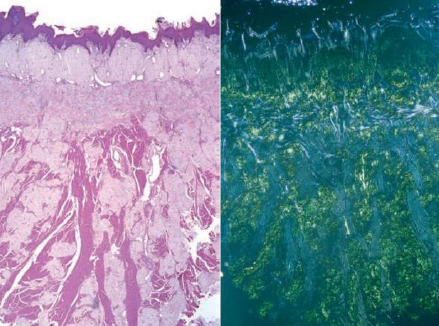

Oral Graft versus Host Disease (GVHD)

- 骨髓移植造成

- 急性 (3 月內)

- 移植 T cell 攻擊組織